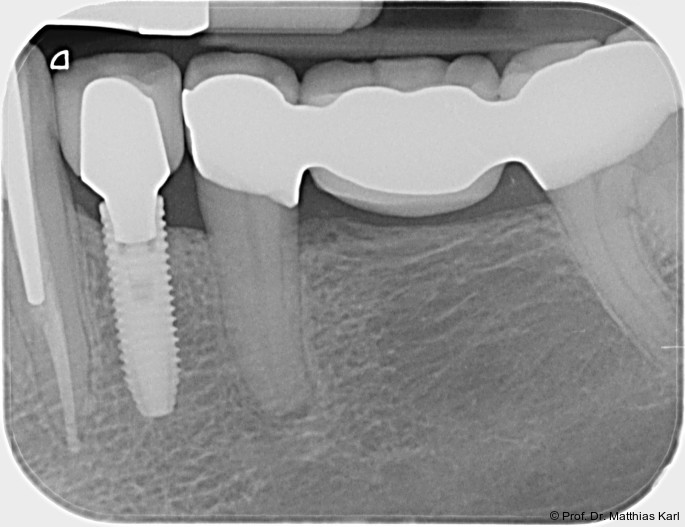

Zur Reduktion der Knochenkompression, insbesondere der bukkal gelegenen Lamelle (Abb. 3), werden derzeit Implantate mit dreieckigem Querschnitt10, 12 sowie Implantate mit zervikal reduziertem Durchmesser16 angeboten. Diese scheinen jedoch im Gegensatz zur subkrestalen Positionierung (Abb. 4a–c) von Implantaten23 keine signifikanten Vorteile zu bieten. Bohrprotokolle, welche sowohl auf das jeweilige Implantatsystem als auch auf die vorliegende Knochenqualität abgestimmt sind, haben ebenfalls das Ziel, zu hohe Einbringdrehmomente zu vermeiden.

Aus prothetischer Sicht ist die Verlässlichkeit der Implantat-Abutment-Verbindung (Abb. 5), die einer hinreichenden Dauerfestigkeit unter Wechsellast bedarf, entscheidend. Kritisch ist hier das Erreichen von Wandstärke im Implantatkörper, welcher zudem die Verbindungsgeometrie und die Abutmentschraube aufnehmen muss. Häufig wird daher die zervikale Außengeometrie dentaler Implantate an die Notwendigkeiten der Innenverbindung angepasst, was zu flacheren, nicht schneidenden Außengewinden führt, wohingegen aus knochenphysiologischer Sicht im zervikalen Implantatanteil schneidende, tiefe Gewindegänge vorteilhafter wären, um dem härteren, kortikalen Knochen zu begegnen.